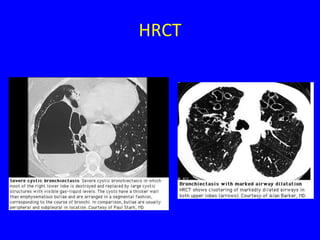

HRCT

• Sensitivitiy ~97%

• Findings

–   Airway dilation

–   Lack of tapering of bronchi

–   Bronchial wall thickening

–   Mucopurulent plugs or debris

–   Cyst

–   Pneumonia, LAP, emphysema

• Distributions

– Upper lobe

– Central distribution

Radiol Clin N Am 43(2005) 513-542